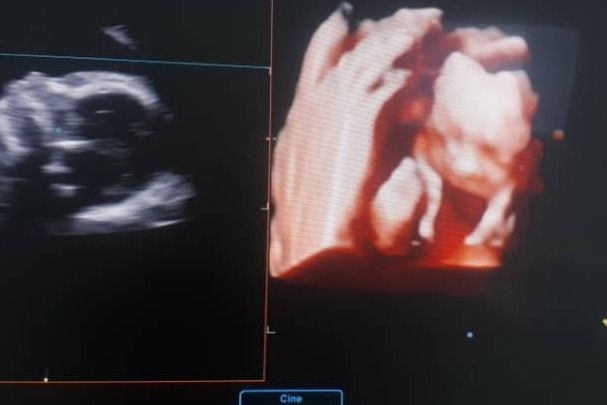

۲۰هفته بودم رفتیم به اتفاق همسرم برای انجام سونو انقدر اطلاعات کامل از وضعیت جنین داشتیم اقای دکتر مهربون خیلی خوشش اومد ازمون و برای اینکه ما خیلی دلمون میخواست صورت ماه نی نی ببینیم اونم با دستگاه 3dچهره نازتو نشونمون داد خیلی خوشحال بودیم عمر مادر